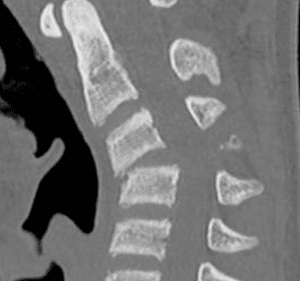

Schwannoma cervico dorsal premedular

Masculino, 66.

Dolor tipo puntada dorsal, interescapular y precordial.

Comenzó a caerse arrodillado de manera espontánea.